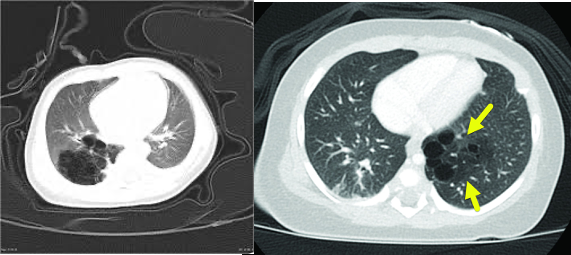

정상 trachea: O-shaped cartilage가 잘 보임

tracheomalacia: cartilage의 일부의 결손, 호기때 collapse되는 소견

진단 및 검사: 기관지내시경 (tracheal ring의 소실부위, 호기 시 collapse되는 기도 확인)